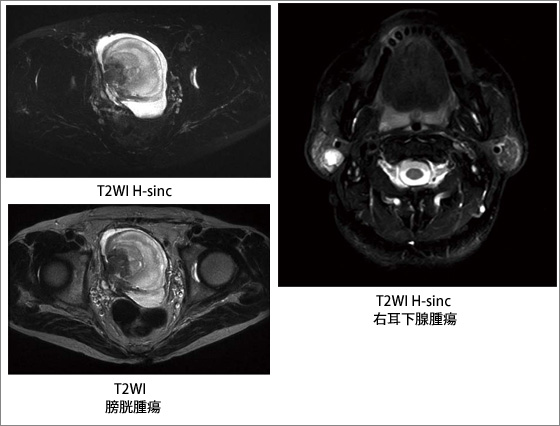

図6に,脊椎領域と体幹部のH-sincによる脂肪抑制画像を示す。H-sincでは,広範囲で高い脂肪抑制効果が得られている。図7は,膀胱腫瘍と右耳下腺腫瘍の脂肪抑制T2WIであるが,磁化率による不均一の影響を受けやすい頸部領域においても良好な脂肪抑制効果が得られている。

図7 H-sinc脂肪抑制の臨床適用例